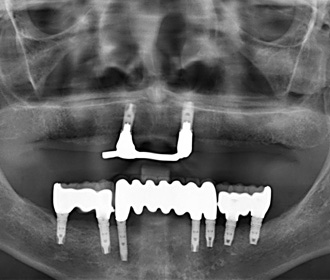

当医院では、アストラインプラント、ZimVieインプラント、Straumannに対応しており、今までの安価なサードパーティー製のものとは一線を画する適合精度、機能性、審美性、破損時の独自の保証システムに基づいて採用しており、良好な臨床実績、成績を得ています。全ての歯牙を失った方でも、全てをインプラント治療で、元々あったご自身の歯牙と全く同じ機能、審美回復できるケース、現在、総入れ歯をご使用中で、その入れ歯にご不満をお持ちの方も、数本のインプラントと入れ歯を組み合わせる治療(インプラントオーバーデンチャー)で格段に機能回復可能なケース、さらに、ブリッジのように歯牙を削らず、単独で処置するケースなど、多彩に応用可能です。

当入れ歯でお困りの方はご相談下さい。様々な解決方法がご提案可能です。

ゼスト・ロケーターシステムは通常のインプラントに接続して入れ歯を安定させるシステムです。また、専用インプラントを使用することにより、今までよりも低コストでの治療が可能です。

インプラント治療例